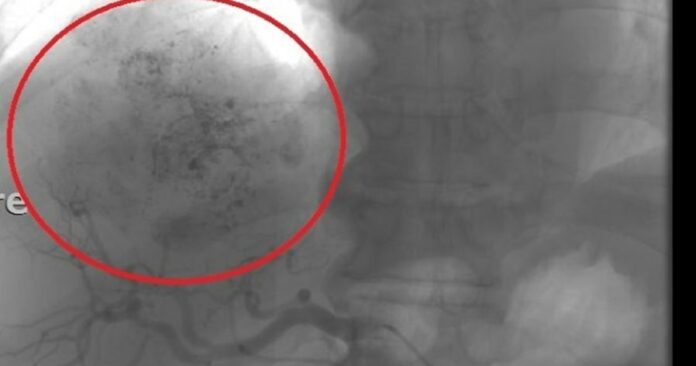

钱政弘后来再检查电脑断层,确认病人肿瘤的状况,结果一照发现「肿瘤缩小」,原本是3.5公分竟变成1.8公分。医师询问中间是否有做什么治疗?家属说,中药或西药都没吃,但回想了一下,病患儿子猜测,可能是因为「果菜汁」的缘故,是邻居分享对肝脏不错的食谱,以川烫的地瓜叶,加入4分之1的洋葱和4分之1的苹果打成汁,每天空腹服用约1个多月。

只是问题就出在急性肠胃炎、引起肾衰竭,因此钱政弘还是请患者先暂停饮用果菜汁,但过了半年至1年再追踪,发现肿瘤整个都消失了。虽然使用的食材多少与抗氧化或抗癌有关,但这个神奇的过程,仍让医师直呼,真的是「一团谜团。」